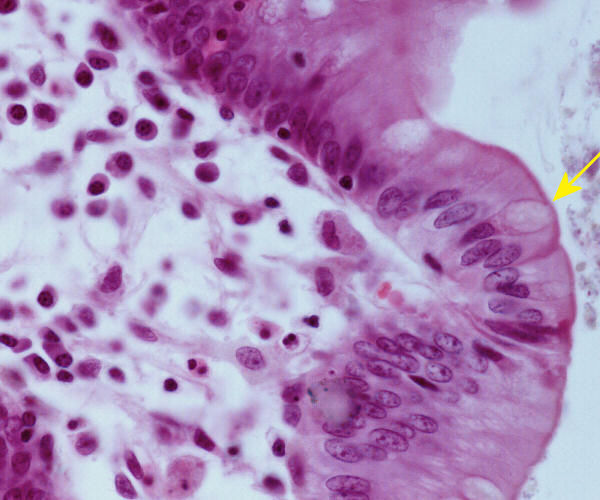

High magnification of the colon

© mei 2007 marius loots